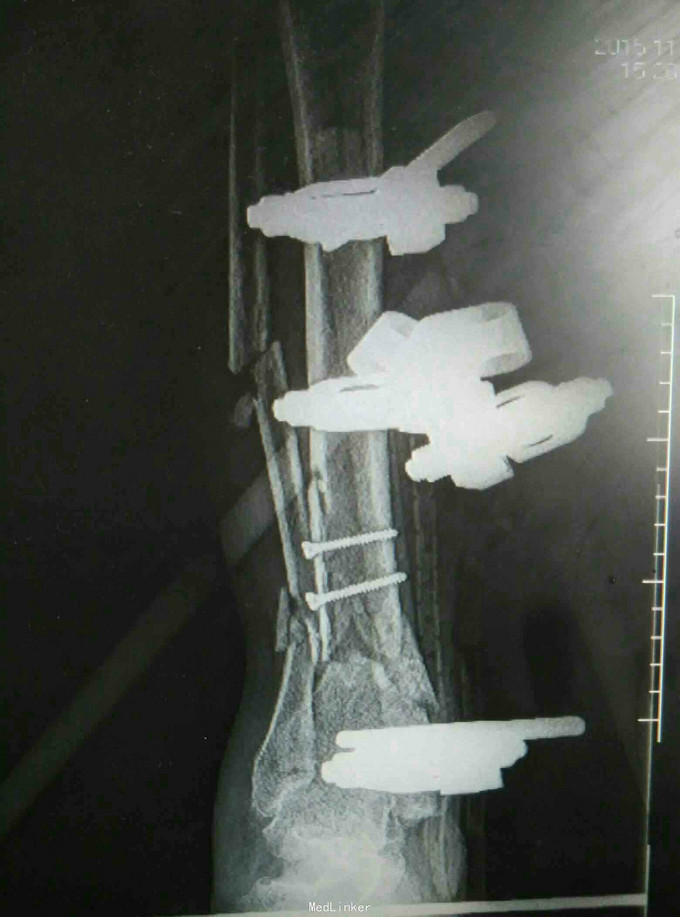

车祸致昏迷伴全身多处出血12小时 患者因车祸被撞后昏迷,伴有全身多处损伤出血,右小腿可见骨外露,患者于当地医院行补液输血,患肢清创包扎石膏外固定后送入我院。

查体:昏迷,平车推入病房,因昏迷骨盆挤压分离实验无法配合,患者双上肢被动活动可,右小腿绷带包扎,解开纱布见胫骨骨外露,可闻及异味,对侧下肢被动活动可。 辅查:摄片提示右股骨干骨折,右胫腓骨骨折

诊断:右股骨干骨折 右胫骨开放性骨折 右腓骨骨折 治疗:开放性骨折清创,骨折外固定架固定

随访:定期换药,注意预防钉道感染,定期复查视情况拆除外固定。 讨论:患者昏迷入院,颅脑也有损伤,下肢开放骨折入院时已出现感染迹象,行彻底清创,行外固定支架固定。对软组织情况不佳的患者切忌盲目内固定,特别是在胫骨跟骨这些紧贴皮肤的部位。